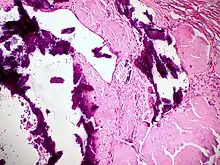

Dystrophic calcification (DC) is the calcification occurring in degenerated or necrotic tissue, as in hyalinized scars, degenerated foci in leiomyomas, and caseous nodules. This occurs as a reaction to tissue damage,[1] including as a consequence of medical device implantation. Dystrophic calcification can occur even if the amount of calcium in the blood is not elevated, in contrast to metastatic calcification, which is a consequence of a systemic mineral imbalance, including hypercalcemia and/or hyperphosphatemia, that leads to calcium deposition in healthy tissues.[2] In dystrophic calcification, basophilic calcium salt deposits aggregate, first in the mitochondria, then progressively throughout the cell. These calcifications are an indication of previous microscopic cell injury, occurring in areas of cell necrosis when activated phosphatases bind calcium ions to phospholipids in the membrane.